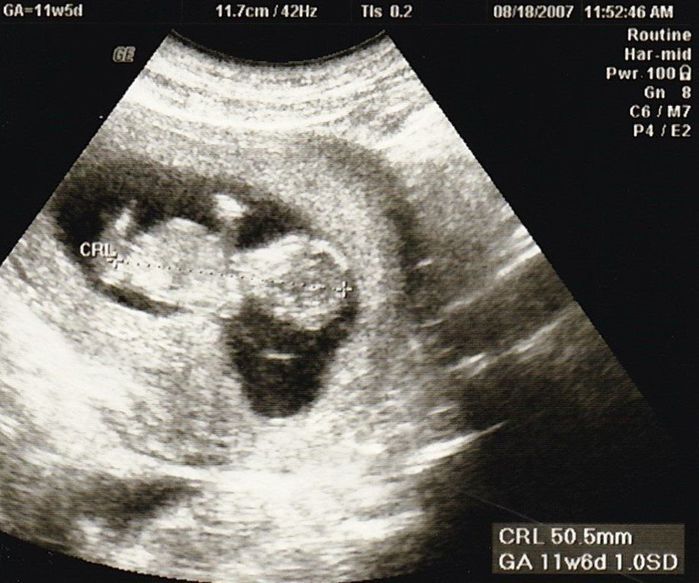

妊娠11週目のエコー写真

産院では、動画で赤ちゃんが動く映像を見せてくれて、検診に行くのが楽しみでした。

この頃、胎児染色体検査(ダウン症かどうかの検査)をするかを決めたり、“ソフロロジー法”の資料を読んだりすることで、私はどういう出産をしたいかを考えるようになりました。(胎児染色体検査はその結果によって産むか産まないかを考えることをしたくなかったので、受けるのをやめました。)